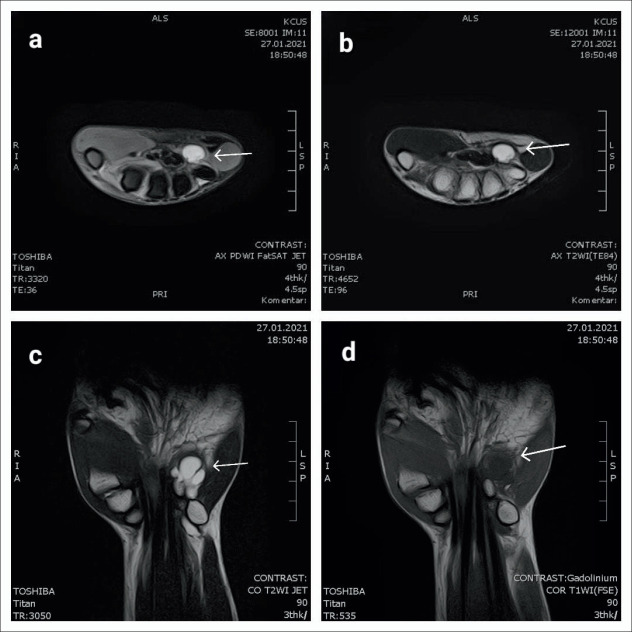

Discussion: After a thorough medical history and physical examination, the diagnosis of the syndrome is made, and ultrasound and magnetic resonance imaging (MRI) testing are used to determine the origin of the neuropathy. A ganglion cyst was identified pathohistological one month following the surgical excision of the soft tissue tumor. In order to hasten the patient's nerve recovery, physical therapy was recommended, and the patient was monitored for the following two years. After two years of treatment, the patient has made a very good recovery of the functionally damaged hand, as determined by a modified Bishop scoring method for evaluating functional ulnar nerve recovery.

Conclusion: In virtually all cases, early surgical intervention can lead to an outstanding functional recovery. If the symptoms are more severe and continue or get worse for more than three months, early surgical intervention is the gold standard for treating Guyon's canal syndrome. If soft tissue formations are compressing the ulnar nerve in Guyon's canal, MRI is thought to be the gold standard for diagnosis.